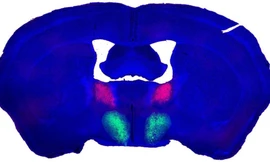

TPO - Công tắc “ham muốn tình dục” được phát hiện trong não của chuột đực khiến ham muốn tình dục của chúng trở nên quá mức. Các nhà khoa học cho rằng, con người có thể có một công tắc tương tự.